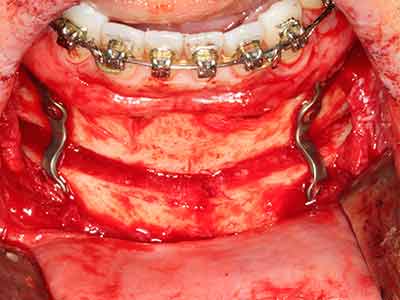

Abb. 13: Bei diesem 52-jährigen Patienten ist bei 4 mm UK-Restknochenbreite während des Bone Splittings auf eine ausreichende Wasserkühlung zu achten.

Abb. 14: Einbringung von vier konischen RSX-Implantaten (Bego Implant Systems, Bremen).

Abb. 15: Die röntgenologische Ein-Jahres-Kontrolle zeigt stabile Verhältnisse des Knochenniveaus.

Abb. 16: Auch intraoral stabile Verhältnisse mit Einbettung der Implantate in keratinisierter Gingiva.

Knochengewebe ist nicht nur rein mineralisch, sondern auch in wesentlichen Anteilen aus Kollagenfasern aufgebaut. Dies gewährleistet neben einer guten Druckfestigkeit eine gewisse Flexibilität, welche für die Durchführung von Augmentationen genutzt werden kann. Bei der klassischen Expansionsplastik im Sinne eines Bone Splittings wird der atrophierte Kieferkamm in seiner Längsachse gespalten und nach Erreichen einer ausreichenden Osteotomietiefe vorsichtig aufgedehnt (Abb. 13-16), idealerweise ohne den Kiefer wesentlich zu deperiostieren (Brugnami, Caiazzo et al. 2014, Stricker, Fleiner et al. 2014). Bewährt haben sich Schrauben- und Plattensysteme mit zunehmender Expansionsdistanz, um die beiden Knochenlamellen unterhalb der Bruchschwelle voneinander zu distanzieren. In der Regel werden Restknochenbreiten von mindestens 3-4 mm gefordert (Chiapasco, Zaniboni et al. 2006), um eine ausreichende Flexibilität und knöcherne Bedeckung der einzubringenden Implantate zu gewährleisten. Ggf. kann eine ein- oder beidseitige vertikale Entlastungsosteotomie die Flexibilität verbessern. Als Alternative zur klassischen Technik wurde eine Kombination mit weiteren augmentativen Techniken vor allem auf der bukkalen Seite beschrieben.

Mittels Piezosägen erfolgt die Anlage des Splittings besonders schonend und ohne wesentliche Dimensionsverluste, so dass sich keine signifikanten Unterschiede von Implantaten im gesplitteten Kiefer im Vergleich zum nicht defizitären Alveolarkamm gezeigt haben (Chiapasco, Zaniboni et al. 2006, Danza, Guidi et al. 2009). Gerade beim lokal begrenzten und tiefen Splitting ist jedoch stets auf eine ausreichende Wasserkühlung zu achten, um thermische Belastungen in den apikalen Osteotomiebereichen zu vermeiden.